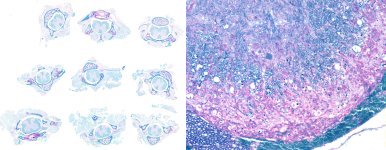

Experimental autoimmune encephalomyelitis (EAE)

Here the spinal column is fixed intact, demineralized, and trimmed into 2 mm thick segments. Segments are positioned in casettes in 3 x 3 arrays between biopsy pads for processing, and are embedded as positioned at trimming. This allows the distribution of lesions over the length of the spinal cord to be determined